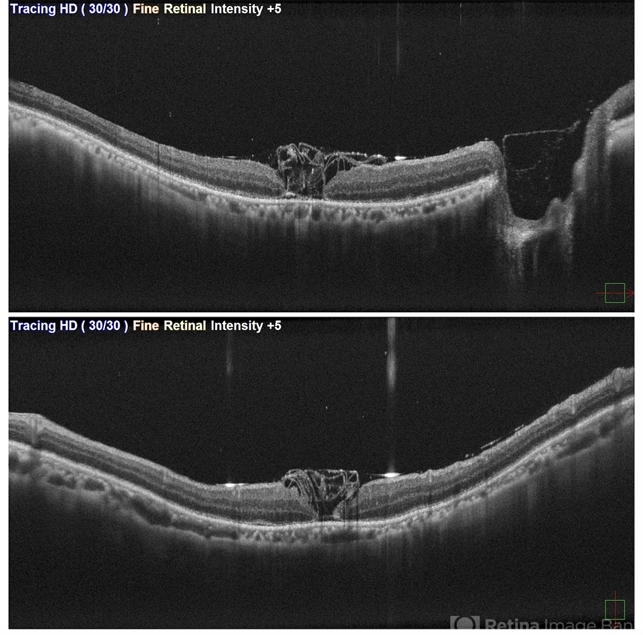

- This is first post op day OCT of patient showing stuffed ILM in macular hole ,who underwent Vitrectomy with inverted ILM flap with silicon oil insertion in a case of RRD with FTMH.